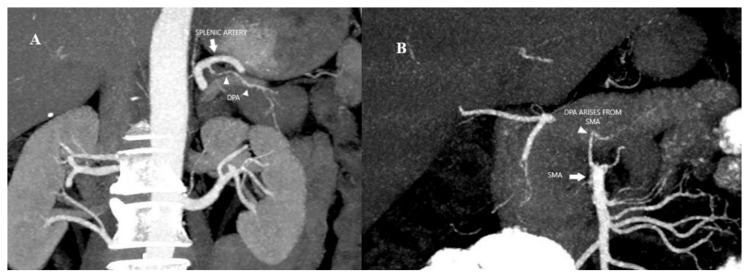

Background/objectives: The aim was to investigate the association between variations in the dorsal pancreatic artery (DPA) and intrapancreatic arcade anatomy with Whipple procedure outcomes and postoperative complications.

Results: After excluding cases that did not meet the study criteria, a total of 284 patients were included in the study. DPA was visualized in 55.98% (159/284) of patients, while the intrapancreatic arcade was observed in 25% (71/284). The most common origin of the DPA was the splenic artery in 69.2% (n = 110) of patients, followed by the superior mesenteric artery in 17.6% (n = 28). The frequency of intrapancreatic arcade anatomy variations was as follows: type 1: 28.2% (n = 20), type 2: 49.3% (n = 35) and type 3: 22.5% (n = 16). Arcade type 4 anatomy was not detected. Postoperative pancreatic fistula (POPF) complication was found to be statistically significantly higher in patients with type 3 anatomy (p = 0.042). The 90-day mortality and long-term mortality rates did not differ among the groups based on the variations in both DPA and intrapancreatic arcade anatomy types.

Conclusions: Patients with intrapancreatic arcade type 3 anatomy had a higher risk of POPF complications. Determination of preoperative arcade type by computed tomography (CT) angiography may help to predict the risk of POPF.